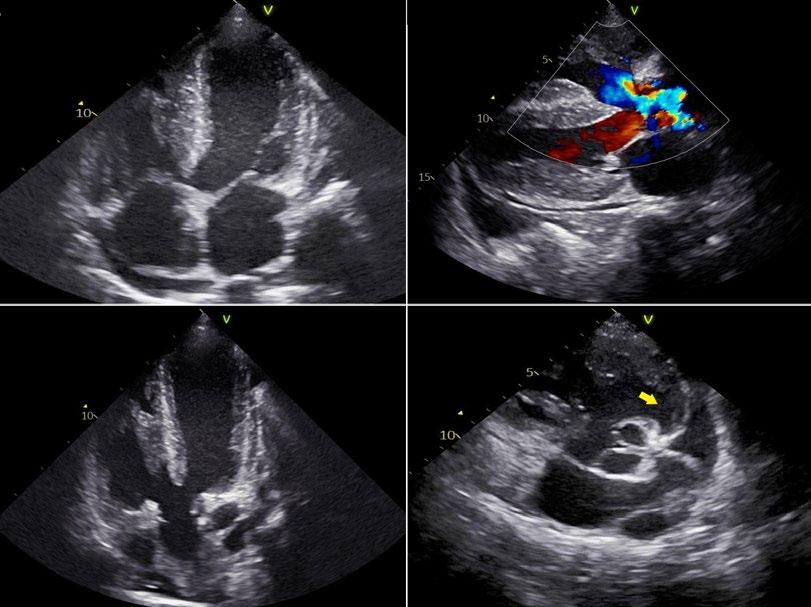

EMJ Cardiology 13.1 2025 by European Medical Journal - Issuu